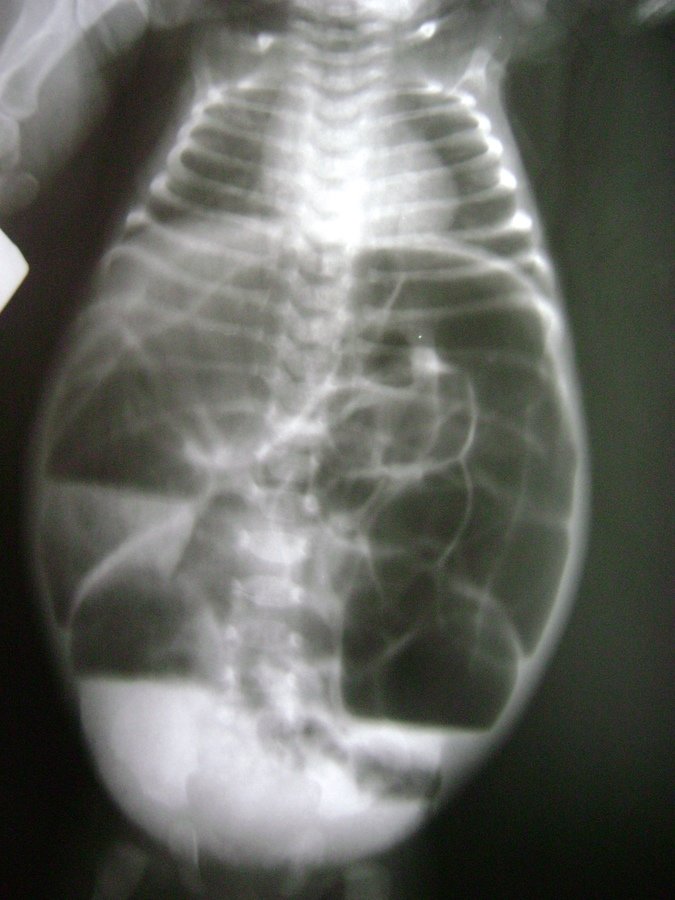

♀L. 0jr - Tractie bij heupdysplasie